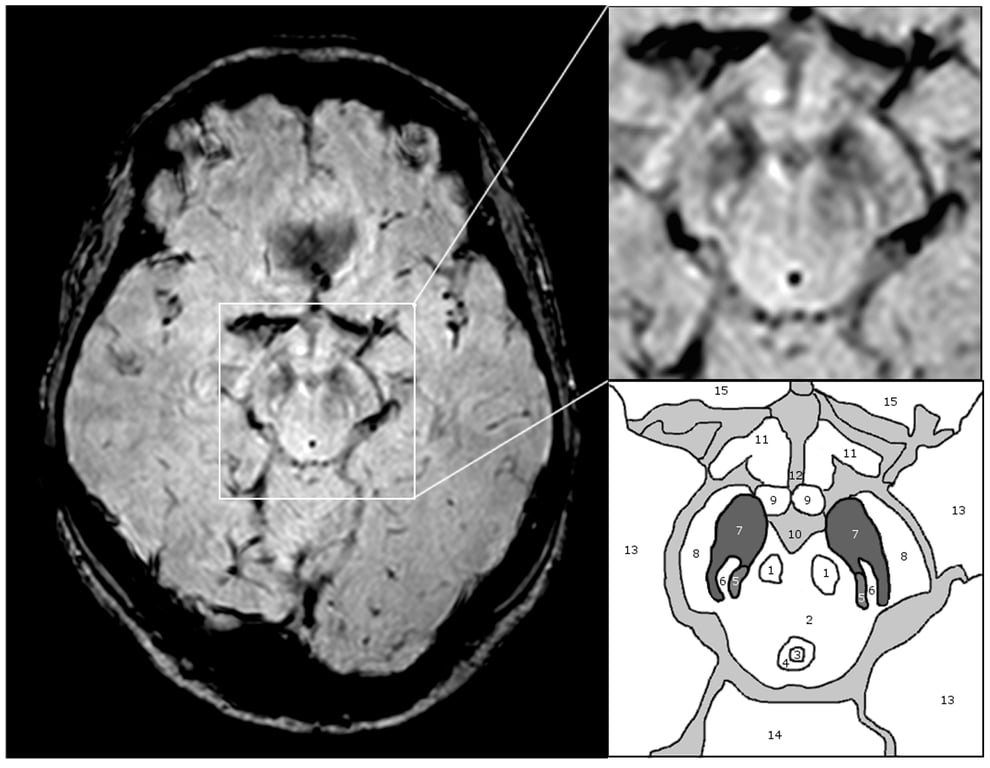

Tajemství Parkinsonovy choroby se začíná odkrývat: vědci poprvé vidí samotný spouštěč